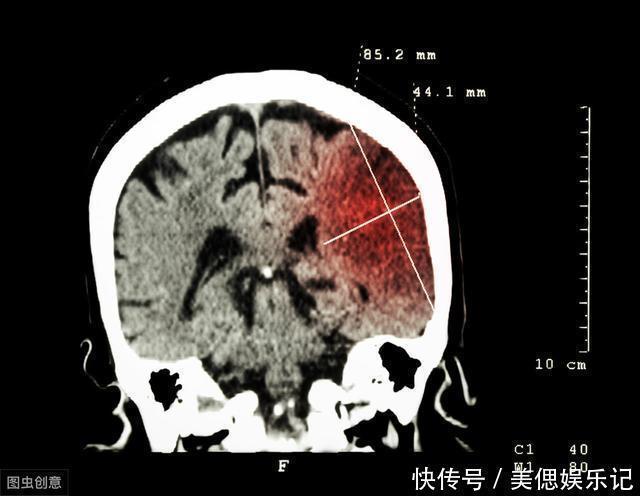

血管堵塞常见危害:血管堵塞可以发生在各个部位,如果发生在大脑,大脑首先会出现供血不足,会导致血栓出现,血栓相信多数人都不陌生,其危害有很多会导致脑梗死出现;除了大脑,心脏也是较常见的血管堵塞的伤害,血管堵塞发生在心脏部位会导致心脏供血不足,患者会出现胸口闷痛的症状,在休息一段时间之后可恢复,但是如果心肌出现缺血性坏死严重,会出现心肌梗塞。脑梗、心梗是血管堵塞最常见的危害,不管是脑梗还是心梗,一旦发作,死亡率非常高。除了心脏、脑梗这些部位,血管堵塞还可以伤害眼睛、肾脏、肺、四肢等等各种器官,因此,日常要注意养血管,避免血管堵塞。